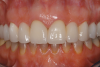

A patient presented with two defective 3-unit fixed partial dentures spanning teeth Nos. 6 through 8 and teeth Nos. 9 through 11 (Figure 7). The defective fixed partial dentures were removed (Figure 8), an impression was made, and traditional provisional fixed partial dentures without ovate pontics were placed. After the impression was sent to the laboratory, the lab technician prepared ovate pontic sites on the stone cast (Figure 9) and fabricated the new definitive bridges. On the day of insertion, the provisional fixed partial dentures were removed (Figure 10), ovate pontic sites were prepared using a teardrop-shaped diamond bur (Figure 11), and the sites were sounded to confirm that there was at least 2 mm from the base of the pontic site to the alveolar bone (Figure 12). The fixed partial dentures were cemented, and the postoperative healing was uneventful (Figure 13).

Although the use of implant-supported crowns in the anterior region has become more predictable, the use of pontics in conjunction with both natural teeth and implants is still common in restorative dentistry. When an ovate pontic design is selected and the site is properly prepared to meet prosthetic biologic width requirements, superior esthetics can be achieved with traditional fixed partial dentures.